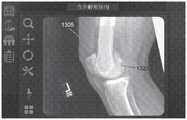

图10A-10C示出了根据实施例的联合配准(co-registering)多个2D图像的过程。10A-10C illustrate a process of co-registering multiple 2D images according to an embodiment.

图11A-11B示出了根据实施例的相对于共同坐标系对准骨的过程。11A-11B illustrate a process for aligning bones relative to a common coordinate system, according to an embodiment.

图12A-12C示出了根据实施例的从关于2D图像的库定向代表性骨的视图的过程。12A-12C illustrate a process for orienting a view of a representative bone from a library of 2D images, according to an embodiment.

图13A-13B示出了根据实施例的相对于至少一个2D图像缩放和重新定向3D骨模型的过程。13A-13B illustrate a process for scaling and reorienting a 3D bone model relative to at least one 2D image, according to an embodiment.

图14示出了根据实施例的修改3D骨模型的轮廓的过程。14 illustrates a process of modifying the contour of a 3D bone model, according to an embodiment.